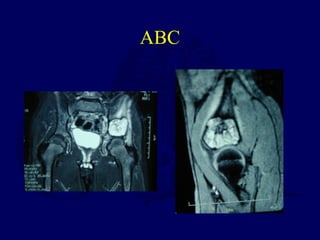

ABC

5 yo female with 1 year of hip pain and 4 prior steroid

injections, progressive coxa vara

•Currettage and bone graft

•+/- internal fixation

•high recurrence

Currettage, biopsy consistent with

aneurysmal bone cyst

1 month after currettage, bone grafting,

valgus/internal fixation, spica immobilization